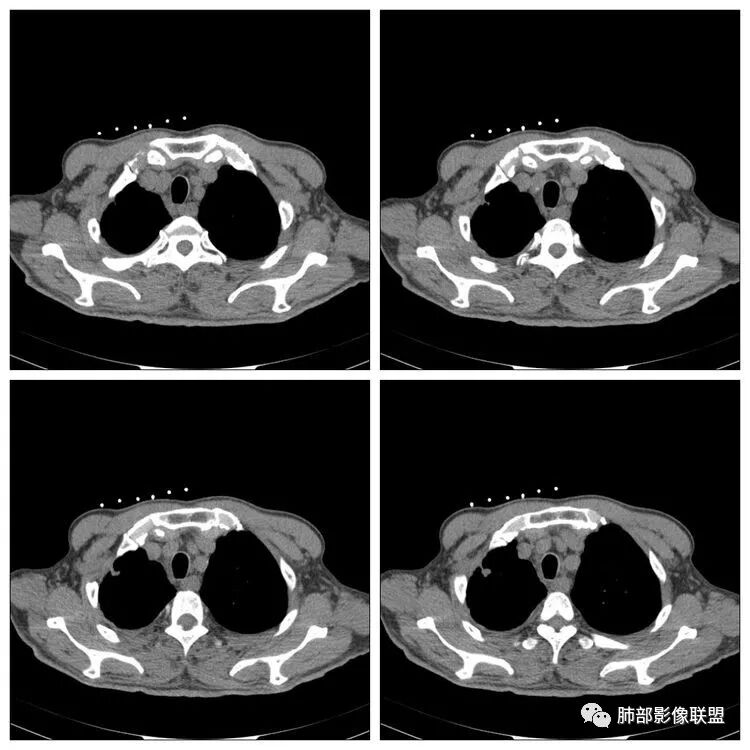

南边:纵隔淋巴结有融合的迹象,边界不清,右侧内乳动脉增粗了很多;怀疑纵隔淋巴结用血很大。有结核的话并不代表不能得癌肿;一般情况下结核附近的病灶呈条索树芽状;综上所述恶性不能完全排除。

这种纵隔右移提示病程较长,腔静脉后见轻度增大淋巴结。

影像可以符合继发性肺结核或其他慢性炎症,或者说它们是存在的。

3.近胸壁处边缘分叶结节影,胸膜凹陷等使人怀疑基础疾病上出现新生物的可能性。

增强扫描是应当的,对于区分结核灶拟或是肺腺癌有较大价值。病理检查还是必要的。